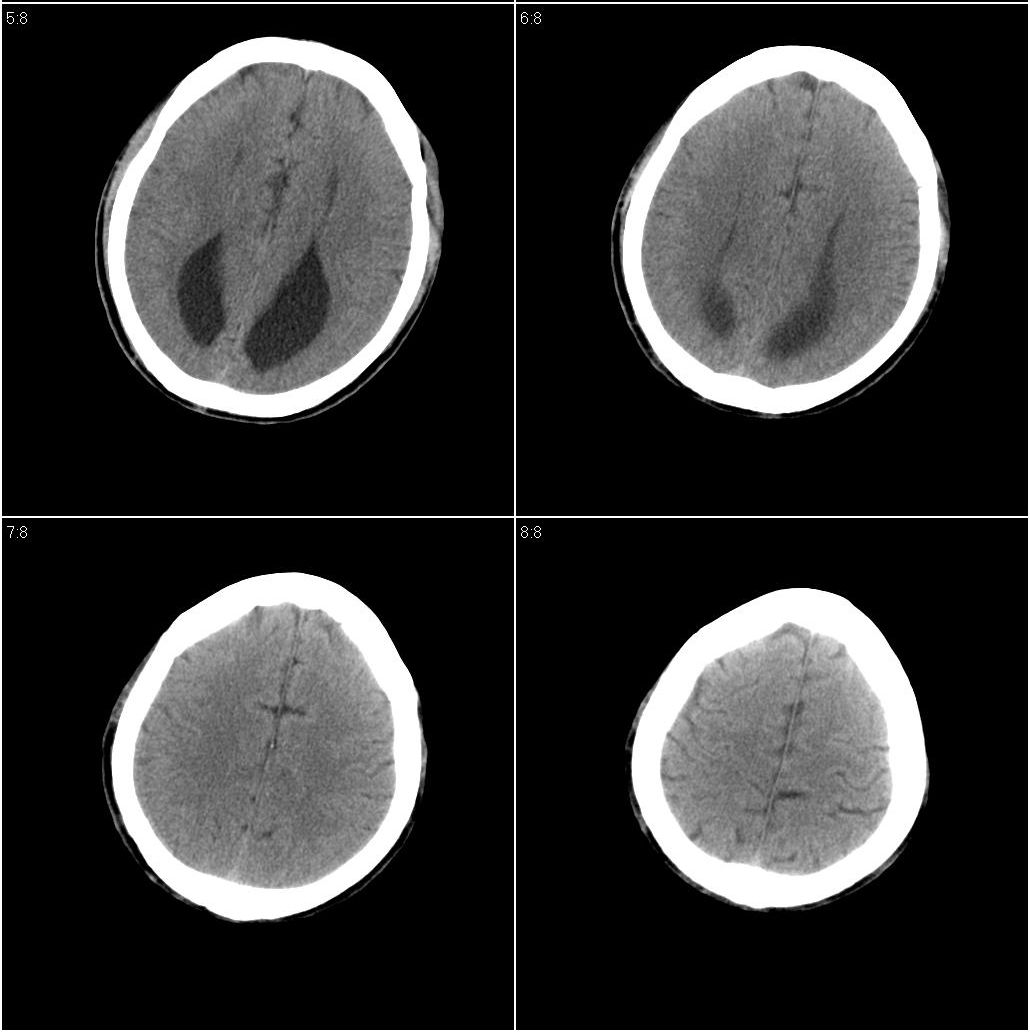

以下是引用牟言科在2008-8-11 20:00:00的发言:[br]ct表现:三脑室扩大并向上移位,双侧脑室体部变小、变直,体部间距扩大,枕角扩张,前纵裂向后延伸。[br]诊断:胼胝体发育不良[br]鉴别诊断:脑积水,侧脑室或三脑室整体扩大,交通性的四脑室也可以扩大,脑沟和脑裂增宽。